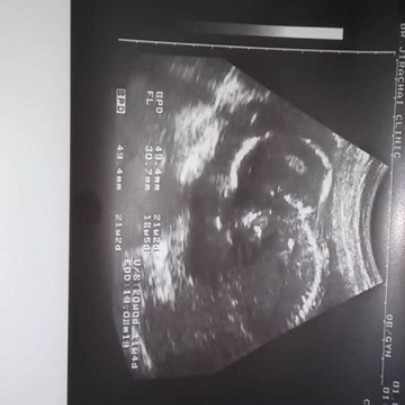

เราสามารถดูได้จากแผ่นอัลตราซาวด์ได้อย่างไรค่ะถึงจะรู้ว่าเด็กน้ำหนักเท่าไหร่อันนี้ซาวครั้งล่าสุดวันที่1ค่ะ5เดือน

วิธีดูนะคะแม่